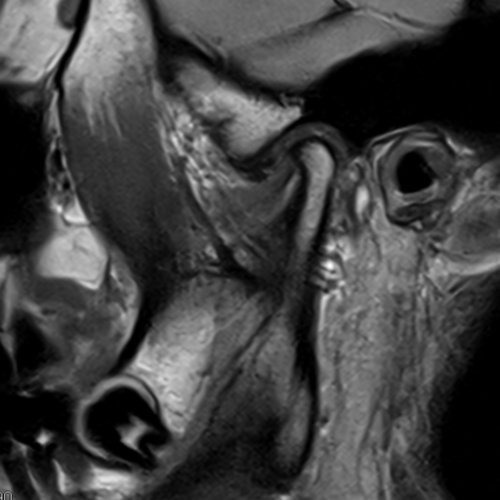

Cet examen est réalisé pour analyser les articulations temporo-mandibulaires, le condyle, le ménisque.

L’examen dure environ 20 minutes. Le manipulateur vous guidera . Il sera nécessaire de rester strictement immobile. Des séquences sont réalisées bouche ouverte et bouche fermée en pondération DP.

L’ IRM des articulations temporo-mandibulaires permets de diagnostiquer:

- les luxations condyliennes

- les déplacements du ménisques

- les pincements condyliens

- les érosions condyliennes

- les troubles de la mobilité condylienne

- les SADAM